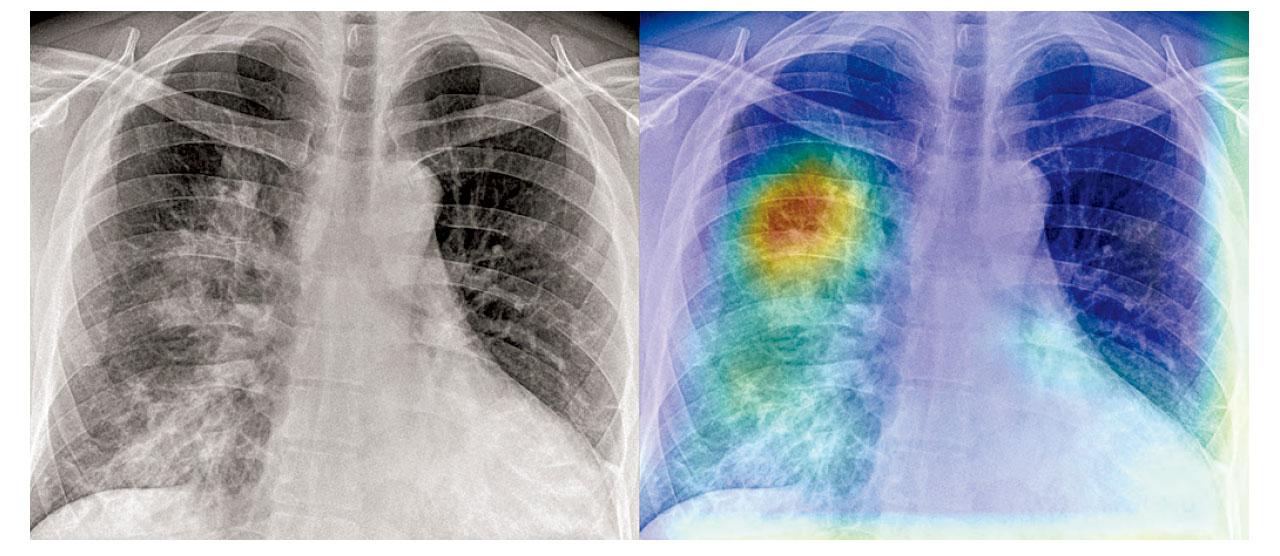

急症室引入AI系統 分析胸肺X光片

發展人工智能(AI)是醫療發展的大趨勢,醫院管理局在普通科門診及急症室引入AI技術篩查胸肺X光片,系統會自動識別病人的肺片。如出現陰影或花白,急症室的人工智能系統會發出紅色警示,而普通科門診的人工智能系統會優先排序,協助醫生篩查肺部病變及高危病人。醫管局會陸續將該技術應用至鼻胃喉安插的X光片檢查,預計明年4月起再擴展至髖關節X光片檢查。

新界西醫院聯網急症科顧問醫生雷俊達指出,每10個急症室病人當中,大約有兩至三個需要照肺部X光片,而AI系統今年1月至11月已在全港18間公院急症室分析了超過66萬張肺片。雷俊達指出,「今年4月1日至10日於天水圍醫院急症室,曾有920個病人照肺部X光片,當中174個個案被AI標示為需關注,經主診醫生即時再三檢查後,證實當中有27個個案肺部呈陰影,其中4個疑似為癌症個案,需再作進一步詳細檢查。」